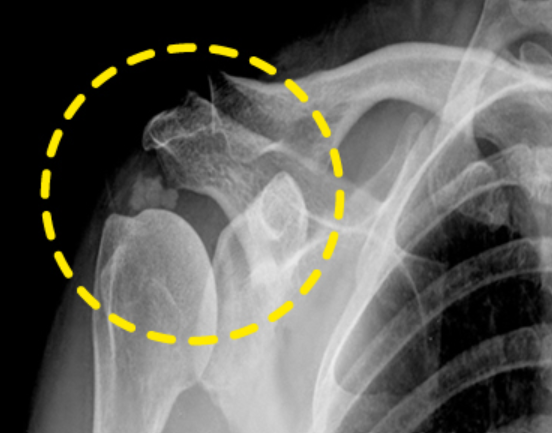

대부분 어깨통증은 50대 이후에서 생기지만 최근에는 여러 이유로 젊은 연령층에서도 많이 생기고 있습니다. 그 중 하나가 바로 어깨 석회질인데 어깨 인대가 탄력을 잃으며 칼슘 성분인 석회가 회전근개 힘줄 내에 쌓이는 질환으로 석회성 건염이라고 부릅니다.

우리가 흔히 힘줄이라고 하는 부위는 회전근개 힘줄을 의미합니다. 석회 성분 대부분은 칼슘이 축적되면서 침전물이 커지면서 자극과 통증을 유발합니다. 힘줄 내부에 석회가 갑자기 분해가 되는데 이 때 견봉하의 점액낭으로 떨어져 나가며 염증 반응을 유발해 통증이 챙기는 것으로 알려져 있습니다.